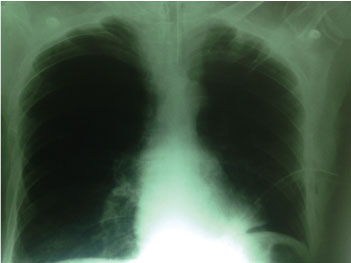

In the chest X-rays of the patient, one of them obtained in the emergency service and the other on admission to the Critical Care Unit, there is no arborization vascular in the lower left field, an image diagnosed as a giant bulla by the specialist in imaging, Pneumonologist and surgeon (Figure 1).

Figure 1: Chest X-rays of the patient, on admission to the Critical Care Unit. There is no arborization vascular in the lower left field, an image diagnosed as a giant bulla.